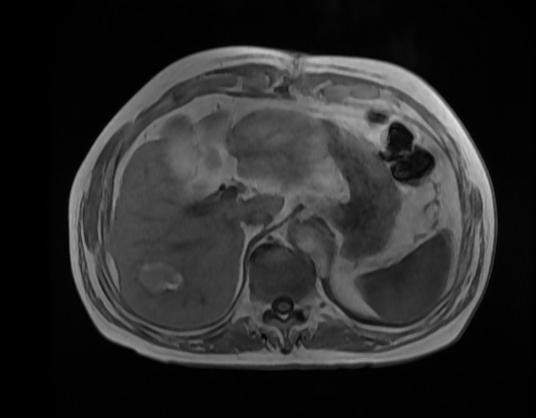

(根据碘油沉积范围精准穿刺完全消融病灶)